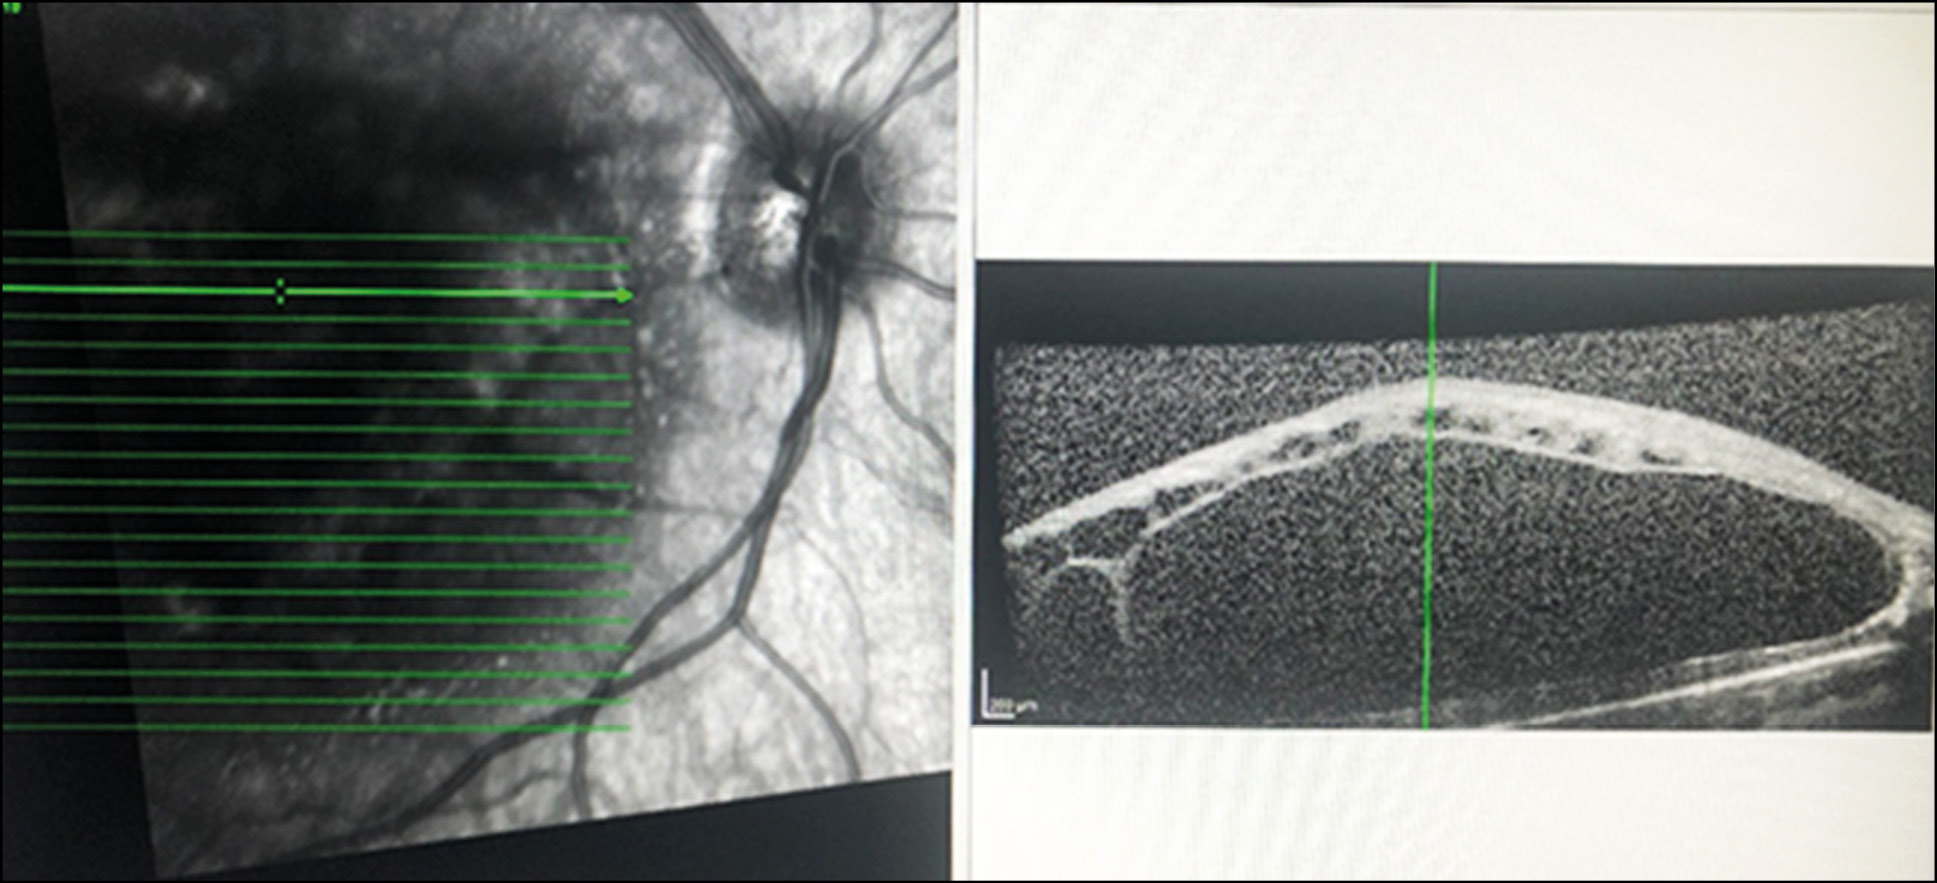

В целом при БК лазеркоагуляция сетчатки была эффективна в 85,8% случаев (у 97 из 113 детей). При наличии сосудистых и экссудативных изменений только на периферии сетчатки достигнуто запустевание сосудистых мальформаций и резорбция экссудата во всех случаях (10 глаз, 100%). При изменениях, захватывающих макулярную зону, эффективность лазеркоагуляции составила 97,3%. Не удалось остановить прогрессирование заболевания только у одного ребёнка с исходным отложением экссудата в 4 квадрантах глазного дна (2,7%). При БК, сопровождающейся локальной отслойкой сетчатки, положительный эффект достигнут в 92,3% случаев. Отслойка сетчатки после проведения лазеркоагуляции прилегла полностью в 16 глазах (66,7%) и в 8 глазах (33,3%) уменьшилась её высота и площадь. Ухудшение состояния в двух случаях (7,7%) отмечено при исходном распространении экссудата в 3-х и 4-х квадрантах глазного дна. При БК, сопровождающейся распространённой отслойкой сетчатки, эффективность лазеркоагуляции составила 90,5%. При этом протяжённость и высота отслойки сетчатки уменьшилась в 17 глазах (89,5%), а в 2 глазах (10,5%) сетчатка полностью прилегла (рис.1 a, b).

Рис. 1, а. Субтотальная отслойка сетчатки при болезни Коатса до лечения.

Fig. 1, а. Subtotal retinal detachment in Coats’ disease before treatment.

Рис. 1, b. Тот же глаз после лечения: остаточные отложения экссудата, участок субретинального фиброза.

Fig. 1, b. The same eye after treatment: residual deposits of the exudate, a site of subretinal fibrosis.